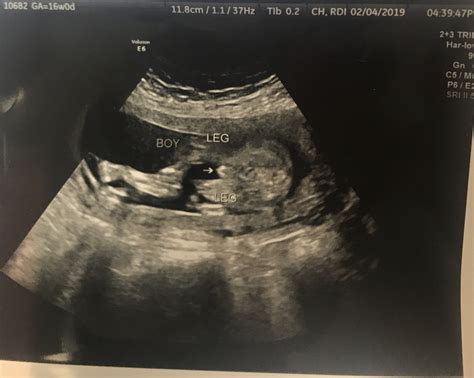

• Gender Determination: In many cases, the baby’s gender can be determined during this ultrasound, although this is not always guaranteed.

Understanding the Ultrasound Images

The 16 week ultrasound provides detailed images of the baby’s anatomy. Healthcare providers will look for specific features to ensure everything is developing normally. Some of the key areas of focus include:

• Limbs: The length and structure of the arms and legs, including the hands and feet.